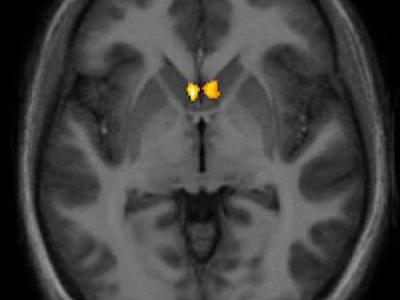

研究发现对大脑适度电击可显著提高数学能力

研究发现对大脑适度电击可显著提高数学能力 据英国卫报报道,最新一项研究表明,...